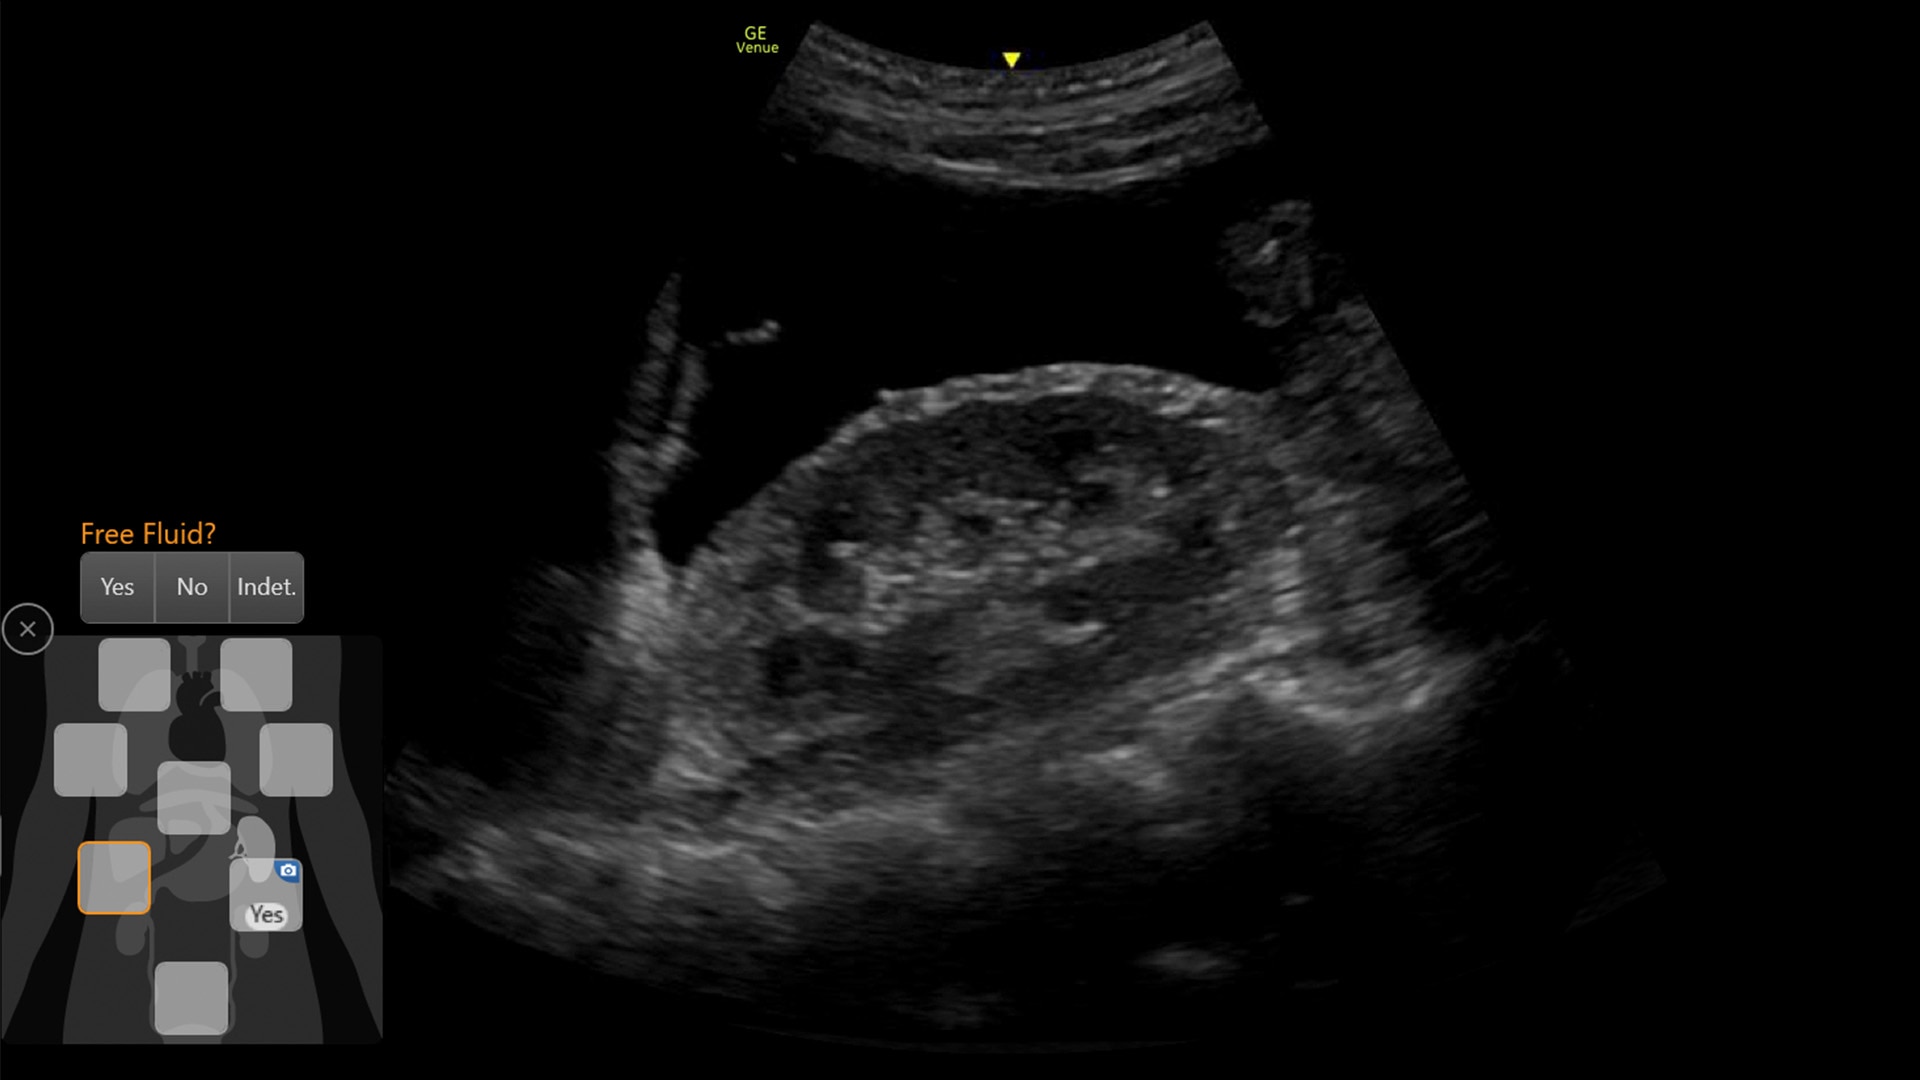

AI-DRIVEN AUTO TOOLS

Advanced and automated clinical tools enabling you to quickly diagnose, treat and determine a care pathway.

Venue Go has been designed and tested to be walk up easy for novice to expert users, and it features a number of AI-enabled automated tools to accelerate clinical workflow while also reducing the fatigue of repeated and difficult tasks. Utilizing proprietary algorithms, we synthesize data from numerous patients to ensure accurate calculations for clinical confidence.